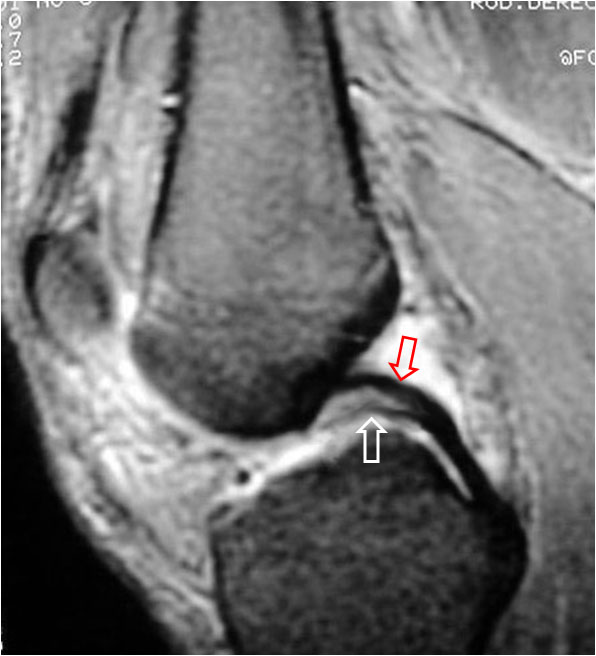

SIGNO DEL DOBLE LIGAMENTO CRUZADO POSTERIOR

Signo de rotura meniscal en los cortes sagitales de Resonancia magnética. El fragmento roto (flecha blanca) se desplaza medialmente y se coloca bajo el ligamento cruzado posterior (flecha roja), dando la imagen de duplicación de éste.